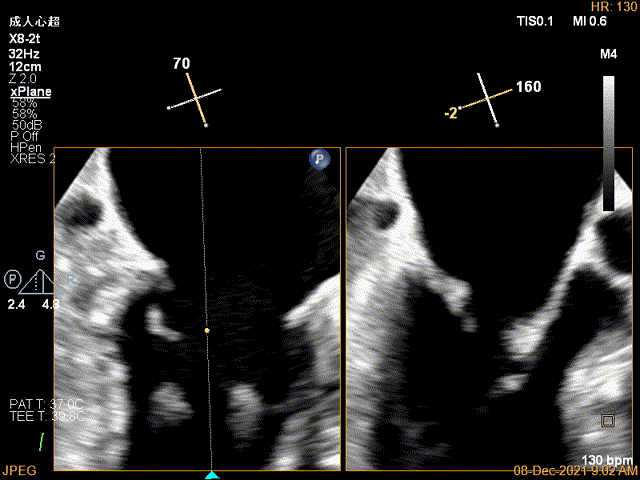

X-plane:下夹子尝试先捕获2区瓣叶

夹子关闭过程中,Color提示2区反流逐渐减少,残余反流位于夹子外侧

x-plane验证前后叶抓捕后bond明显

3D-VIEW验证结果

3D-Color-view验证残余分流位于外侧